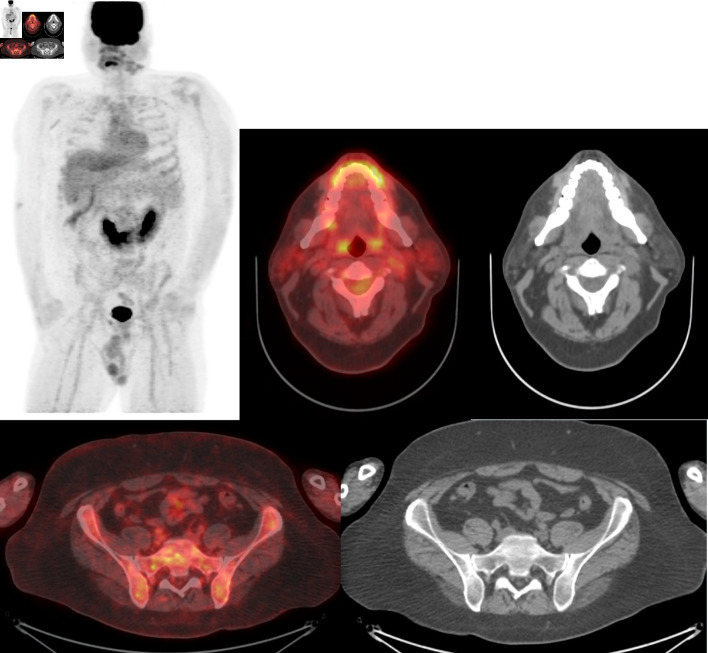

Abstract Image